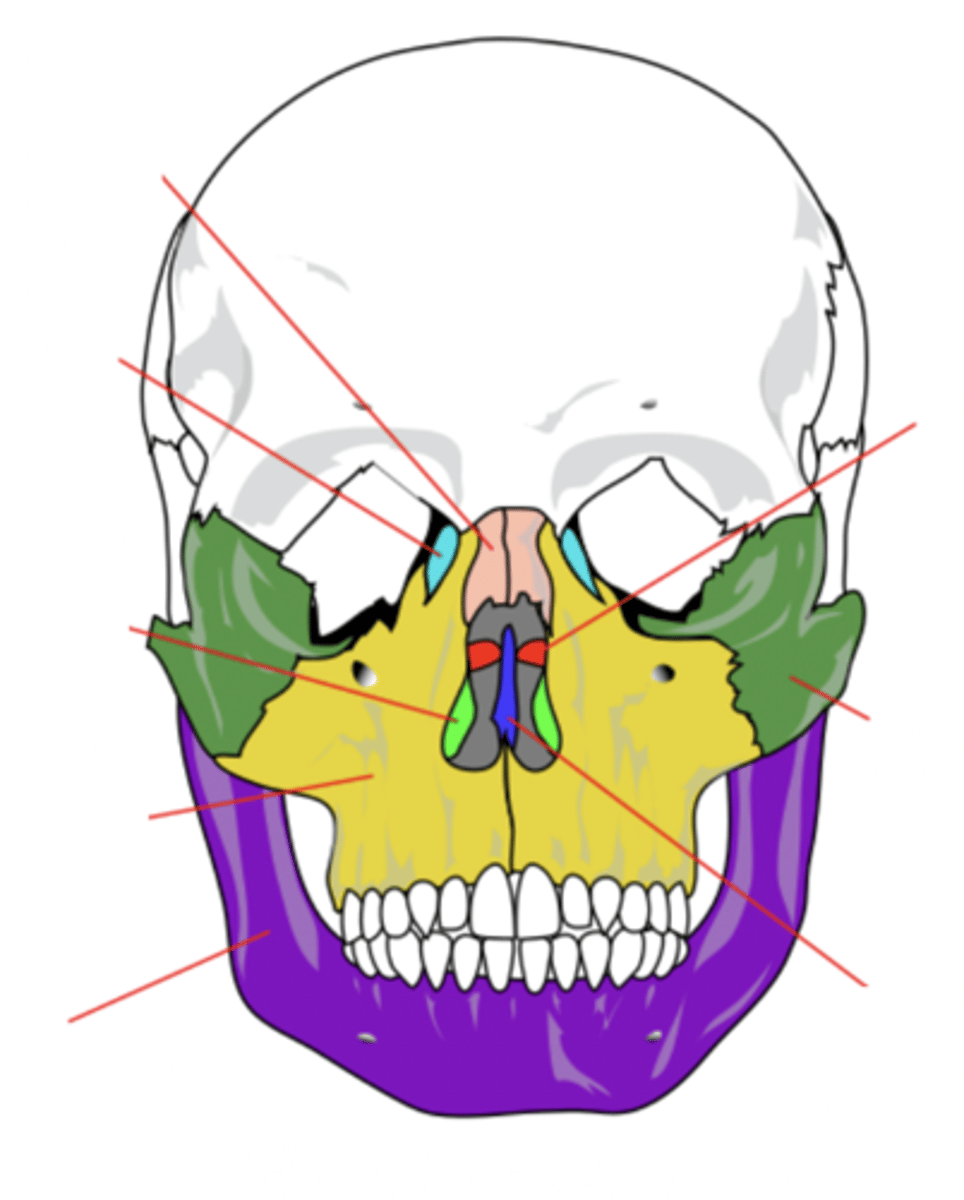

Facial Bones (14)

- Maxilla (2)

- Mandible

- Lacrimal (2)

- Palatine (2)

- Inferior conchae (2)

- Vomer

- Nasal (2)

- Zygomatic (2)

(Many Mammals Like Playing In Very Nice Zoos)

Maxilla Bone (2)

Upper jaw bone (yellow)

Mandible Bone

Lower jaw bone (purple)

Lacrimal Bone (2)

Small fragile bone making up part of the front inner walls of each eye socket and providing room for the passage of the lacrimal ducts (light blue)

Palatine Bone (2)

Bone that forms the hard palate and parts of the nose and orbits (red)

Inferior Conchae Bone (2)

The thin, scroll-like bones that form part of the interior of the nose (light green)

Vomer Bone

Bone that forms the inferior portion of the nasal septum (blue)

Nasal Bone (2)

Bone that forms the bridge of the nose (pink)

Zygomatic Bone (2)

Cheek bone (green)